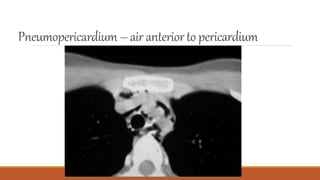

Pneumopericardium– air anteriorto pericardium